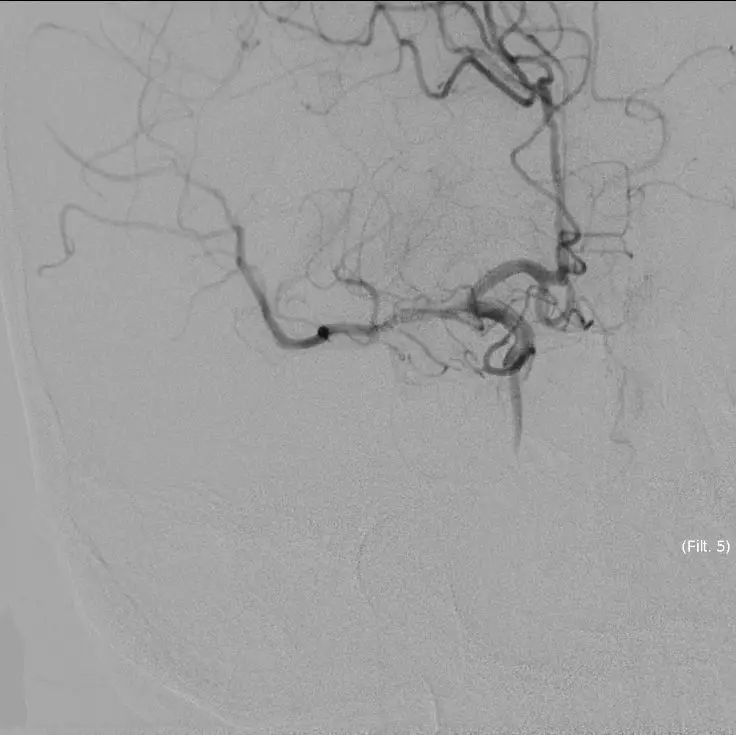

患者症状逐渐加重,头颅MRA示右侧大脑中动脉闭塞,是本次病灶责任血管,目前患者在取栓时间窗内,有行桥接动脉机械取栓指征。与患者家属沟通后全麻下行右侧大脑中动脉取栓术。手术风险及相关注意事项向患者家属告知。

立即DSA(08-03日 13:24分)